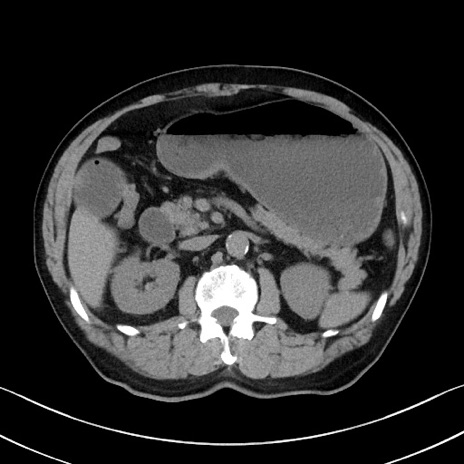

症例35(横断像)

【症例】70歳代 男性

【主訴】腹部膨満、嘔吐

【現病歴】昨日より腹部膨満感出現。本日増悪し、仙痛出現。嘔吐あり、受診。

【既往歴】糖尿病、胆摘後

【身体所見】BP 149/80mmHg、HR 74/min、BT 35.9℃、腹部:膨満、軟、圧痛なし。腸雑音減弱あり。上腹部正中切開瘢痕あり。

【データ】WBC 13500、CRP 1.72